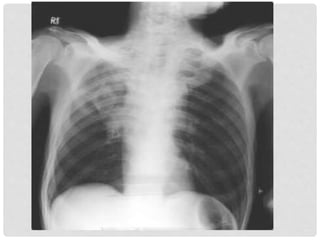

LA ALERGIA Y AL ASMA

• La alergia juega un importante

papel tanto etiología como

desencadenante

• La mayor parte de los niños-

adolescentes con asma son

alérgicos

• Los ácaros son en nuestro medio,

el principal alergeno en el asma

• El polen el principal alergeno para

las enfermedades alérgicas y el

segundo para el asma